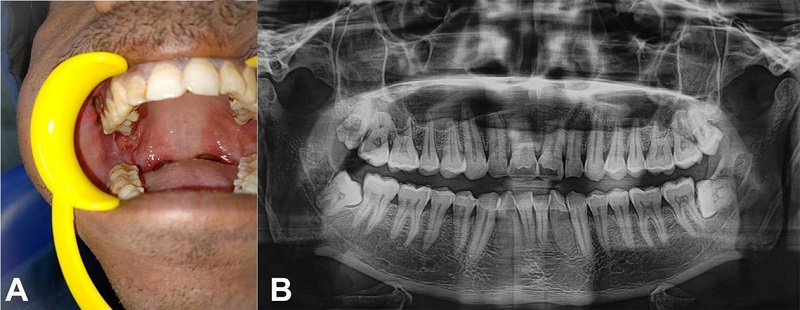

A 29-year-old male sought health care with a painful ulcer on the right inner cheek region that had been present for one month. The patient was apparently normal for a month before seeing an ulcer on the inner side of the cheek’s region. Ulcers were painful and exacerbated by spicy foods. He claimed to be an avid hukkah smoker twice a day for the past five years. One and a half years ago, the patient was treated for tuberculosis and got treatment for it. An ulceroproliferative lesion was seen intraorally on the right pterygomandibular raphe, which was indurated, tender on palpation, and covered with necrotic slough (Figure 1A). On radiographic examination, orthopantomogram detected no soft tissue or bony changes (Figure 1B).